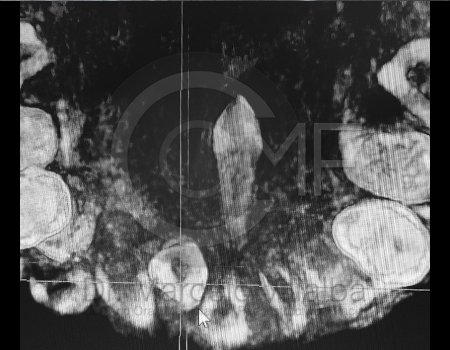

CIRUGÍA ORTOGNÁTICA EN DEFORMIDADES O ASIMETRÍAS FACIALES

Es una cirugía en la que se busca mover el maxilar, mandibular y mentón o sólo una de estas estructuras para alcanzar una combinación médico-odontológica, así llegar al fin estético y funcional del aparato estomatognático y facial.